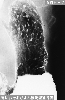

Posted by: Tokyo Pref., Cooperative study between National Cancer Center and Kyushu Cancer Center

Date of entry 2014/02/28

Number of image 47